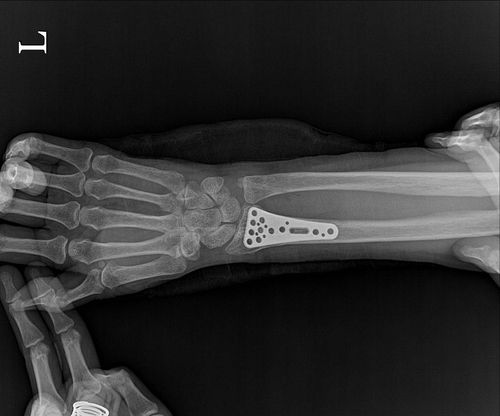

몸속에 남겨둔 철판[피해자 측 제공. 재판매 및 DB 금지] / 사진 = 연합뉴스

하지만 수술 부위의 상처가 아물지 않고 지속적인 통증이 이어지자 의심을 품은 A씨는 9일 후 병원을 재방문했다. 검사 결과 충격적이게도 최대 6cm 길이의 철판이 여전히 손목 안에 남아있었다. 의료진은 작은 철판만 제거하고 큰 철판은 그대로 둔 채 수술을 마무리한 것으로 드러났다.

A씨 측 변호인은 "체내 잔존 철판으로 인한 염증 발생은 물론, 수술 후 X-ray 확인조차 하지 않은 점이 큰 문제"라며 "더욱이 담당 의사는 직접적인 사과도 없이 직원을 통해서만 연락하고 있다"고 지적했다.